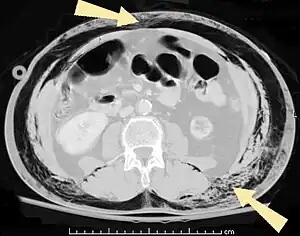

![]() | |

| An abdominal CT scan of a patient with subcutaneous emphysema (arrows) | |